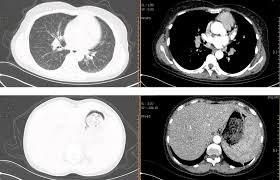

四、 医生如何判断“良性”还是“可疑”?

医生不会凭一句“多发结节”就吓你,而是综合以下 5 个特征👇:

🩺 医生解读:

“多数 3–5mm 小结节都是良性的炎症残影。真正需要关注的,是那些‘单侧、毛刺状、在短期复查中长大的’结节。”

现代高分辨 CT(HRCT)的分辨率极高,能看到0.2mm的结构,